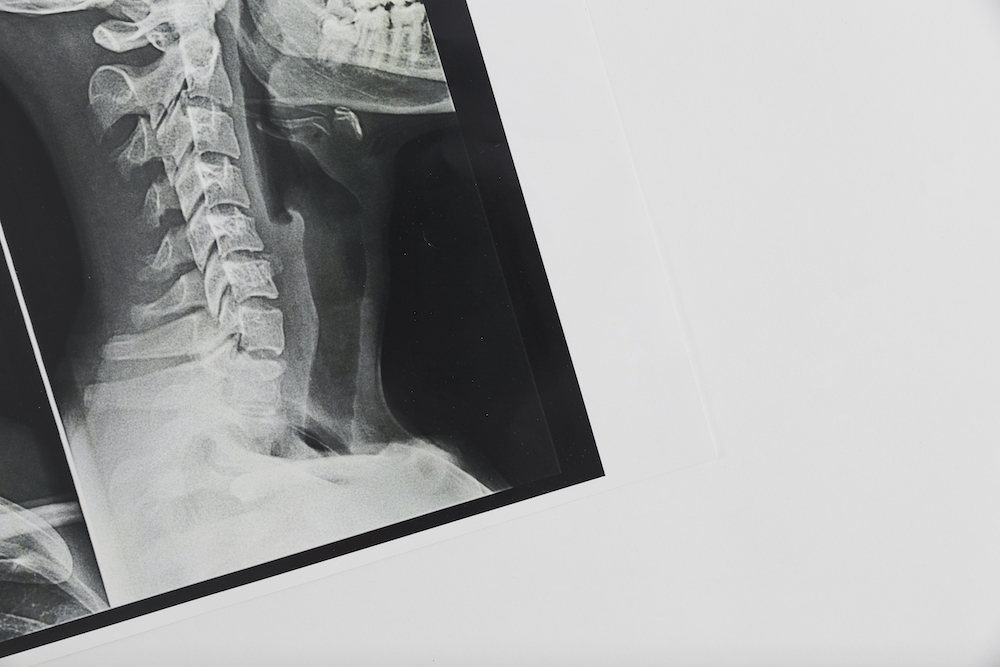

Getting an x-ray of your spine gives us an extremely detailed look at what’s going on with your spine. Many times, this can help us confirm the diagnosis and give us confidence in the right treatment plan to help getting you back to optimal health.

If you’ve been experiencing back pain, neck pain, or headaches, or other discomforts, a spinal x-ray can help us identify the cause and give us a clear path for treatment.

A spinal x-ray can give our chiropractor in Magnolia important information about your spine. The imaging can help diagnose problems with your bones, joints, and discs. A spinal x-ray can also help find problems with the ligaments, muscles, and other soft tissues in your back that are tougher to diagnose without the images.

Spine X-rays can reveal herniated discs, scoliosis, degenerative disc disease, arthritis, spinal misalignments, fractures, and other structural problems. At Southern Wellness Chiropractic, Dr. John Tysdal uses X-rays to guide personalized chiropractic care for patients in Magnolia.